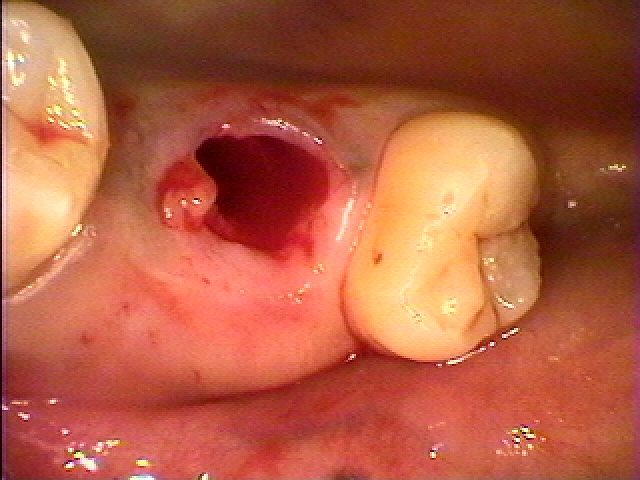

問題の口腔内になります

問題の口腔内になります